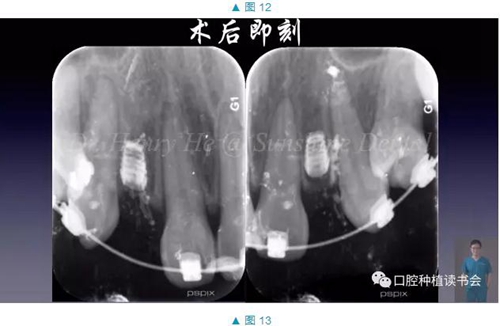

經(jīng)過虛擬種植,我們對鄰牙位置,以及缺牙區(qū)域牙槽骨情況有了深入了解和充分準備,按照這個計劃進行了手術(shù)(圖7-13)

手術(shù)順利,術(shù)后患者未訴疼痛和腫脹。7天拆線,3個月后進行了微創(chuàng)的二期手術(shù),暴露植體,開始進入修復階段。